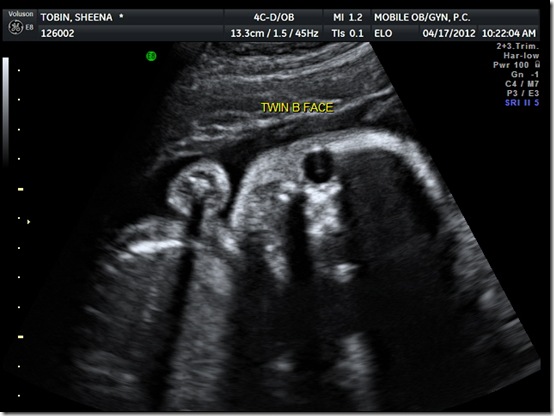

I’ll leave y’all with one last picture. Twin B was very interested in having her pictures taken today and, scary though it kind-of looks, she made sure to look right at the camera, although whether or not she was mouthing “cheese” is debatable: